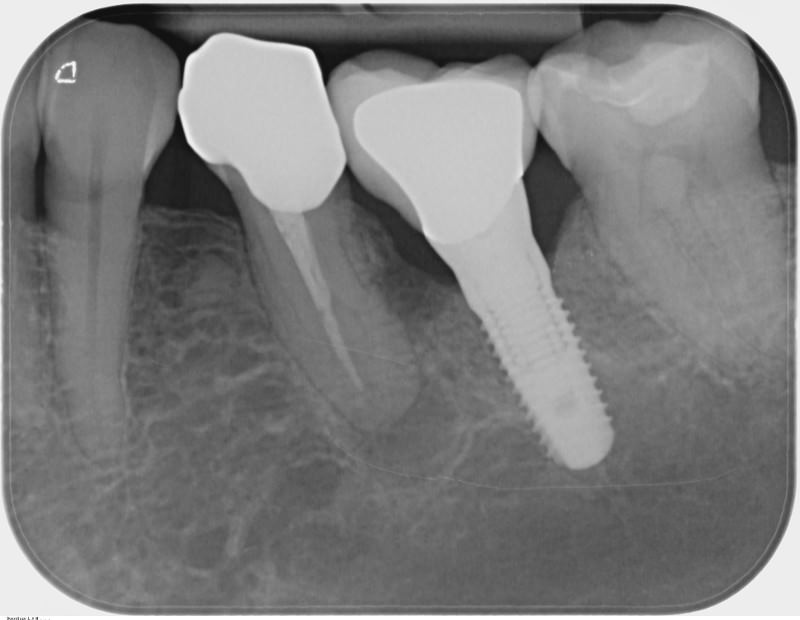

• z.B. Röntgenbilder zur Prüfung durch die zuständige Behörde an die Zahnärztliche Stelle Röntgen gemäß § 28 der Röntgenverordnung,